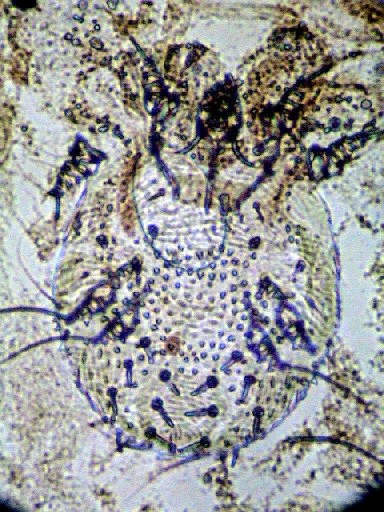

火曜日診療終了間際にいらした方の確定診断が付いたのは、

皮膚から採取した標本の角質層が苛性カリで完全に解けた、7時30分でした。